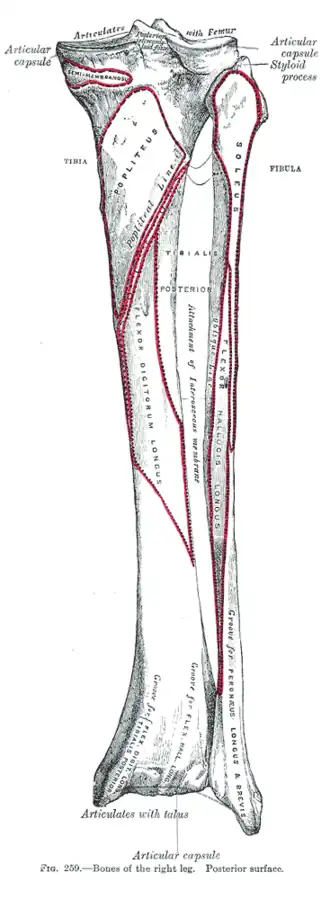

Bones of the right leg. Posterior surface.

Bones of the right leg. Posterior surface. -